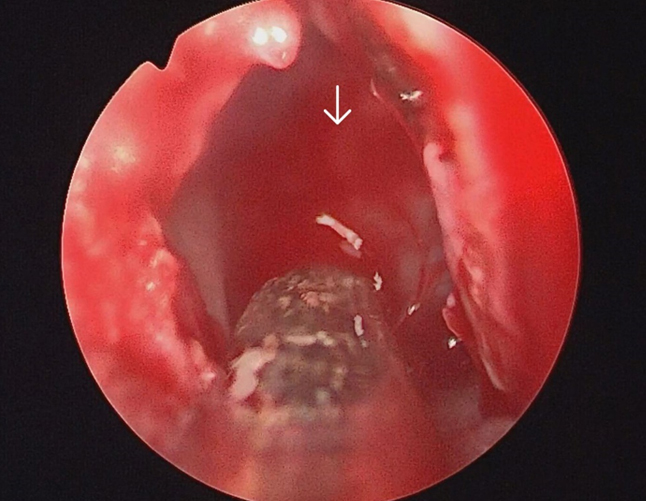

The surgery was performed under general anaesthesia by the first author. Nasal endoscopic examination after administering general anaesthesia showed watery discharge from the region of the left cribriform plate (figure3 B) and the left spheno-ethmoidal recess (figure 4). The surgery proceeded with left partial middle turbinectomy and widening of the sphenoid ostium on the left side. This was followed by left uncinectomy, middle meatal antrostomy, left anterior ethmoidectomy an removal of basal lamella and posterior ethmoidectomy. This was followed by clear delineation of the leak in the left cribriform plate and a wide sphenoidotomy (figure 5). The edematous sphenoid sinus mucosa was removed and the meningoencephalocele was seen in the left lateral recess above the vidian-rotundum line. The sphenoplalatine foramen was identified and the sphenopalatine artery cauterized. The medial aspect of the posterior wall of left maxillary sinus was removed partially. The upper part of the pterygoid process was drilled out and widened laterally exposing the antero-medial temporal lobe and the meningoencephalocele (figure 6) and the continuous csf leak leak identified.

Figure 4. Arrow showing csf leak in the left sphenoethmoidal recess

Figure 5. Arrow showing csf gusher in the left sphenoid sinus after endoscopic left sphenoidotomy.